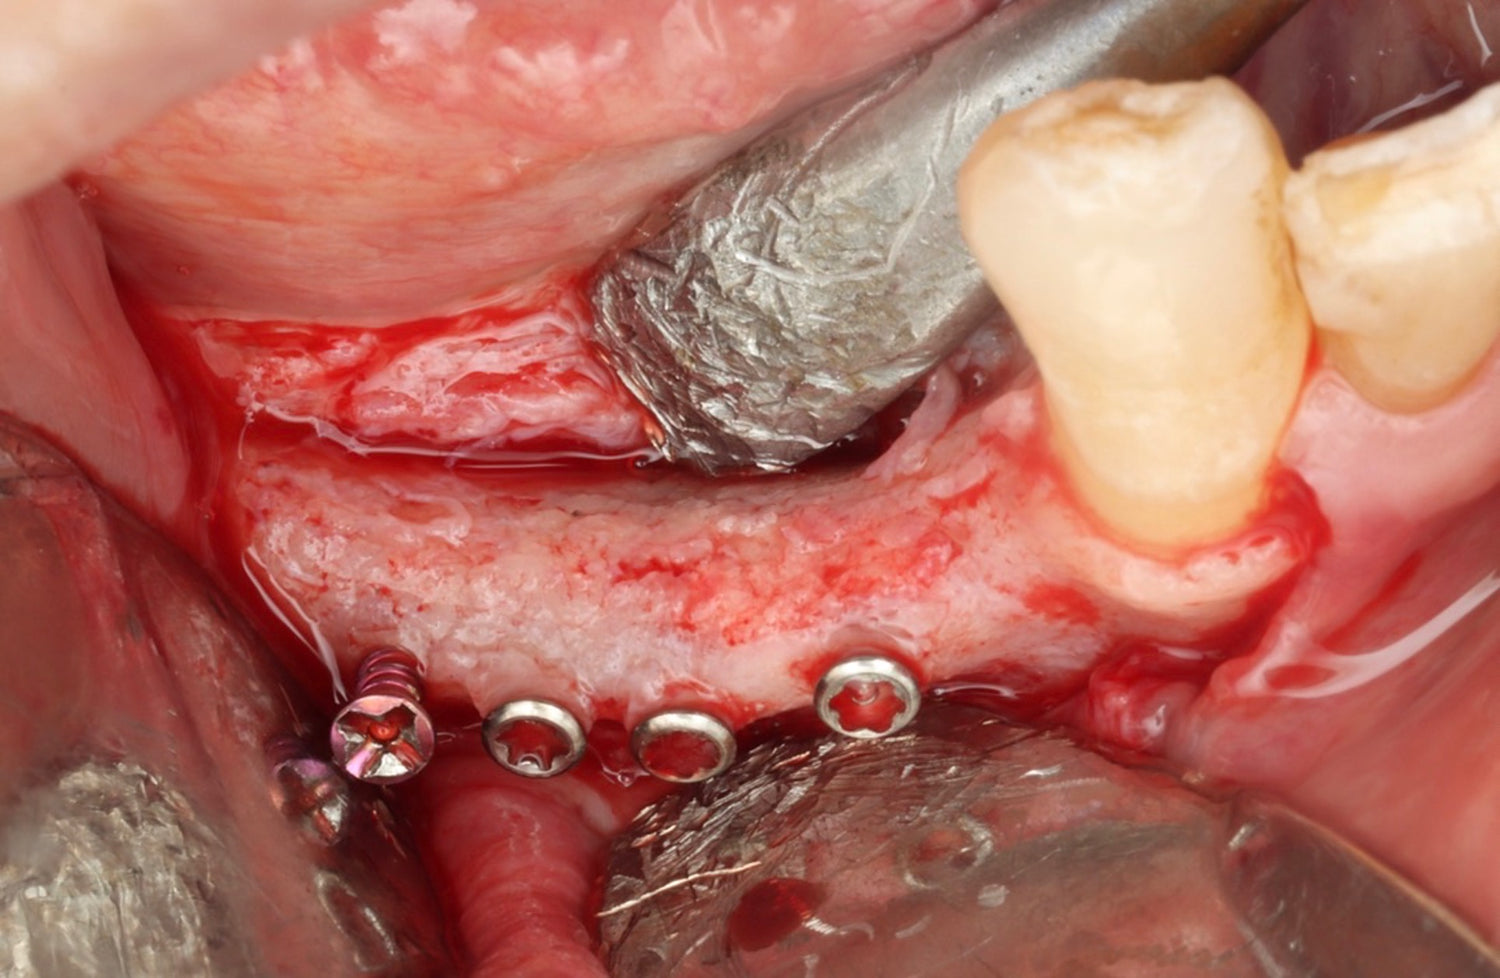

- Learn advanced bone augmentation techniques using autogenous bone plates, from principles to implementation

- Khoury plate